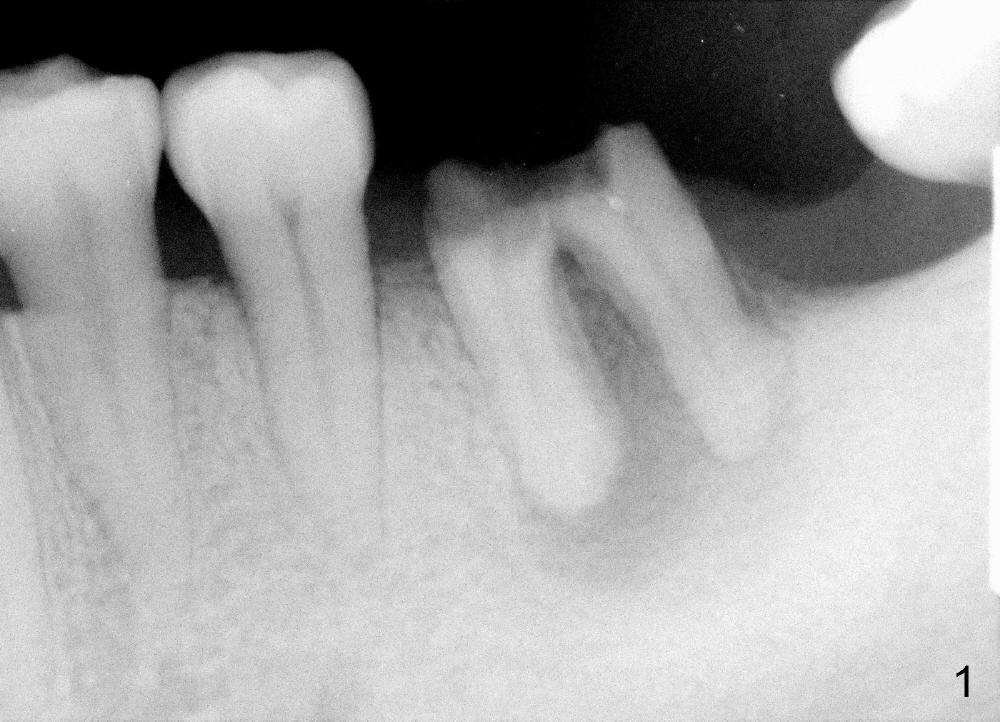

A 46-year-old female patient requests restoration of the lower left 1st molar (Fig.1). Although the patient refuses diabetes treatment, her wounds usually heal uneventfully. Her gag reflex is active. She could not tolerate a removable partial denture, which replaced the missing 2nd molar. Preop PA and CT shows extensive bone loss around the residual roots (Fig.1,2,4). It appears that extraction is simple. Immediate implant should not add too much additional trauma (Fig.3,5). Arrowheads in Fig.3,5 indicate the extent of osteotomy for implantation. With meticulous surgical manipulation, the wound should heal normally.